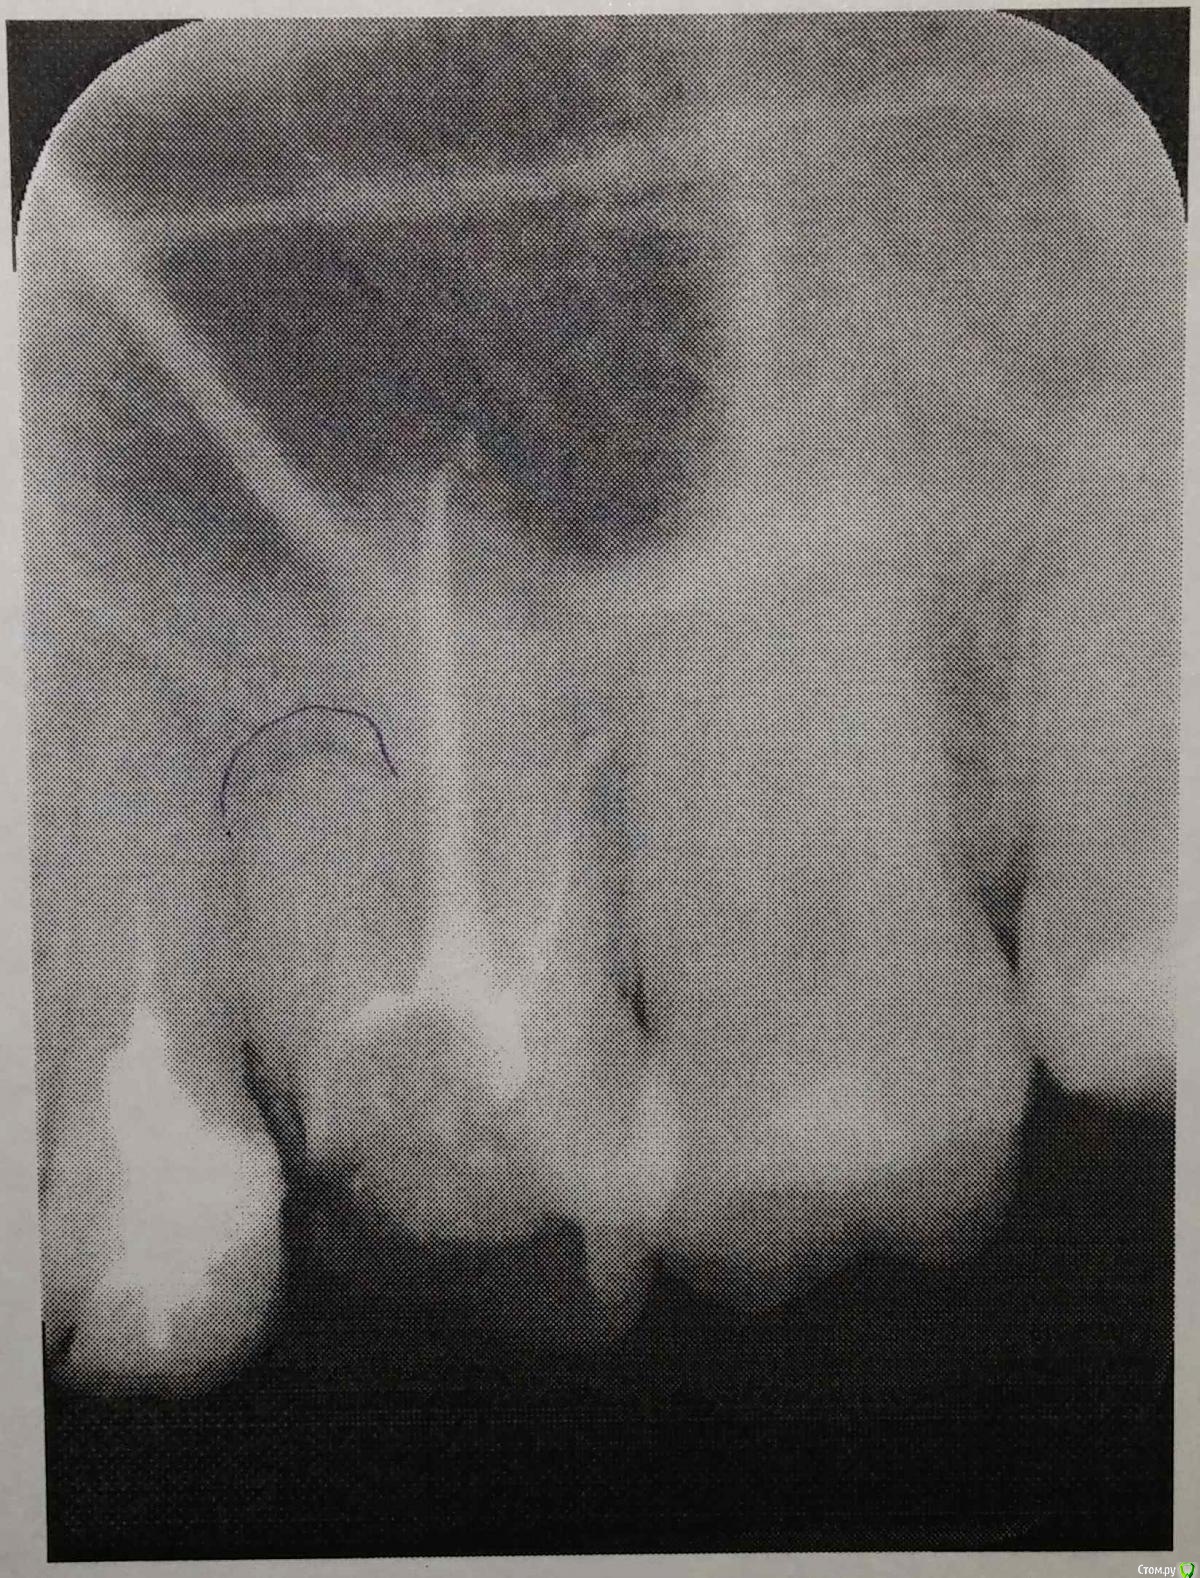

bambuk Опубликовано 1 марта, 2016 Поделиться Опубликовано 1 марта, 2016 И снова здравствуйте!Зуб 26.Один непроходимый канал (цемент?), дважды закладывалось лекарство, первый раз на две недели, второй на месяц (разное, какое не знаю), положительной динамики нет.Есть только итоговый снимок, прикрепил к сообщениюСо слов врача, ни механически, ни медикаментозно пройти канал (инструмент уходит в сторону) и вылечить зуб не удается. Вердикт: адекватному эндодонтическому лечению не подлежит. Можно ли еще как-то попытать счастье? Ссылка на комментарий

DmitrySH Опубликовано 1 марта, 2016 Поделиться Опубликовано 1 марта, 2016 Да, с микроскопом нужно 2 Ссылка на комментарий

ЕленаВалерьевна Опубликовано 2 марта, 2016 Поделиться Опубликовано 2 марта, 2016 +1заодно и 2.5 переделать можно. 1 Ссылка на комментарий